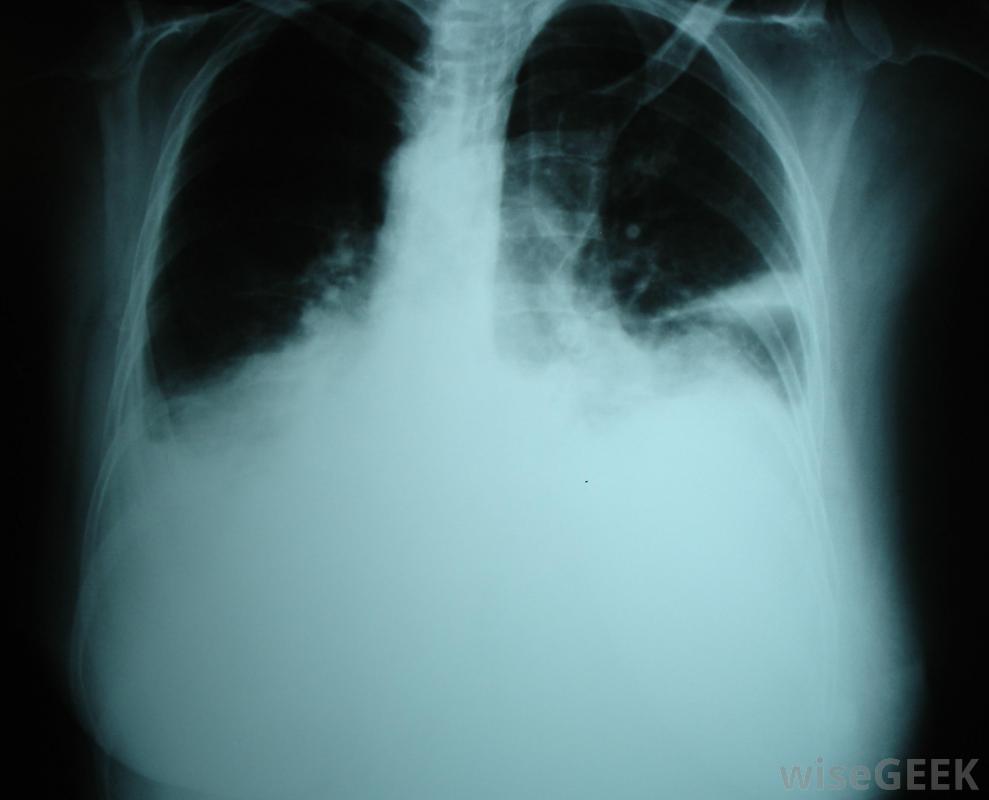

胸腔积液是胸腔内多余液体的积聚,胸腔包围着肺部。正常情况下,胸膜中含有一层薄薄的液体,以保持肺部在呼吸过程中的平稳运动。当有过多液体时,右侧胸腔积液发生在右侧胸膜中,右侧胸腔积液比左侧胸腔积液更容易导致充血性心力衰竭胸腔积液。右侧胸腔积液或右侧胸腔积液的发生,是一种潜在疾病的结果。右侧和左侧胸腔的液位通常不同,称为非对称性胸腔积液。胸腔积液也可孤立于其中一个空洞,称为单侧胸腔积液。右胸腔积液主要与充血性心力衰竭(CHF)有关胸腔积液是胸腔积液在肺部周围胸腔中的积聚。胸腔积液的最初症状通常是当胸腔中的液体达到一定量时大约500毫升。报告的症状包括呼吸困难或疼痛,以及呼吸时胸壁的运动减弱。当胸部和背部被交叉或轻拍时,共振也会减少当用听诊器检查时,呼吸音可能会很迟钝,也可能会有不寻常的声音,如噼啪声或摩擦声,这是由于过多的液体产生的摩擦造成的。如果怀疑这些症状,通常会进行x光或超声波检查以确认诊断

右胸腔积液主要与充血性心力衰竭相关。一旦诊断出右胸腔积液或左胸腔积液,则将一根大针放在背部或胸部取出,这一过程被称为胸腔穿刺术。然后对液体进行分析,以确定液体的成分,以及液体是否渗出或渗出。渗出液表明是全身性的,其中身体的一部分,通常是心脏、肝脏或肾脏,会造成体内液体的整体失衡。渗出液表明肺部或周围有问题,如细菌或病毒感染、栓塞或癌症,需要进一步的检查才能确诊。还有其他类型的原因没有分类,例如自身免疫性疾病和手术引起的积液,但这些并不常见。